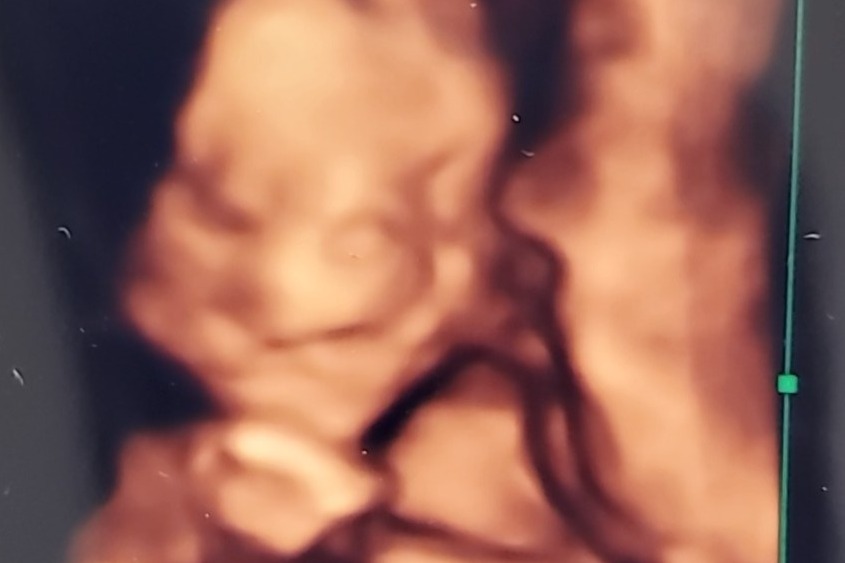

Below is the only picture they will have of sweet Kodiak, we were lucky enough to do fetal photos on March 27, 2021.